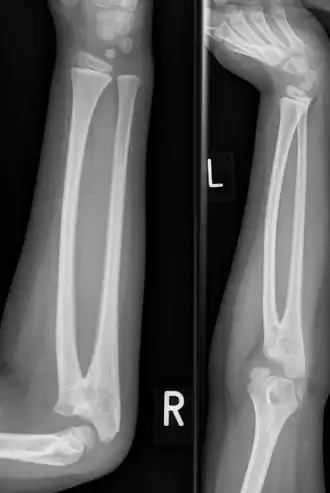

| Sinostose radioulnar congênita em um menino de 7 anos | |

A sinostose radioulnar é uma condição rara em que existe uma ligação anormal entre os ossos do antebraço rádio e ulna.[1] Pode estar presente no nascimento (congênito), quando é o resultado de uma falha na formação dos ossos ou após uma lesão (pós-traumática).[2]

Normalmente causa restrição de movimento do antebraço, em particular rotação (pronação e supinação), embora geralmente não seja doloroso, a menos que cause subluxação da cabeça do rádio.[1] Ela pode estar associada ao deslocamento da cabeça do rádio, o que leva à extensão limitada do cotovelo.[2]